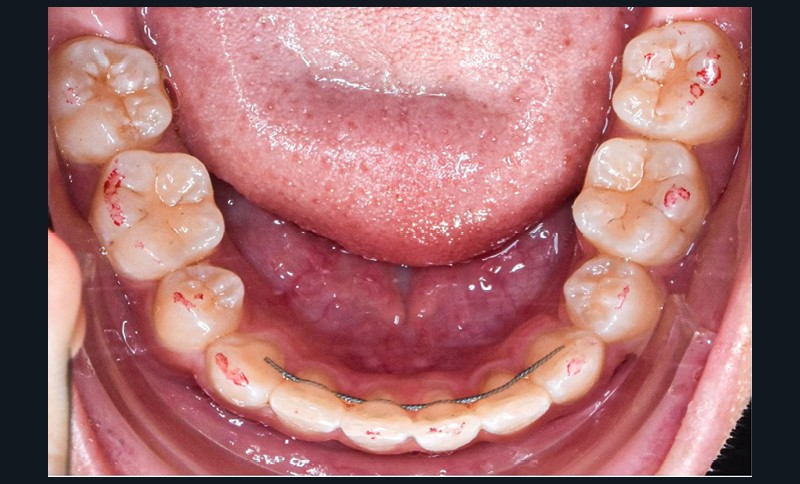

L’objectif du traitement est la correction de la DDA tout en assurant le remplacement de la 21 compromise. Décision a été prise d’extraire 34 et 44, ainsi que 21 et 14. La traction de la 23 a été réalisée à l’aide de forces légères, sur un arc transpalatin (fig. 9). Le nivellement et l’alignement, puis une mécanique par glissement ont permis d’aménager l’espace suffisant à la stratification de la canine. Elle associait un ressort en nickel-titane à des élastiques de Classe II (4 ½ oz, 3/16’’) sur un arc en acier .019×.025. Une phase d’ingression a été réalisée pour ajuster le niveau du bord libre de la canine à celui de l’incisive controlatérale (fig. 10-12).

Les corrections esthétique et fonctionnelle de la canine ont été effectuées par stratifications de résine composite (fig. 13). Au préalable, une simulation numérique de la nouvelle forme à donner à la canine a été élaborée. Une fois imprimée, cette simulation a servi à fabriquer une clé en silicone moulant les faces palatines des incisives. Cette clé a été garnie d’une fine couche composite de masse « émail » (Miris, ColteneR, Suisse) qui a été polymérisée une fois replacée en bouche pour constituer une coquille palatine. Afin d’élargir légèrement le profil d’émergence, des matrices (Slick Bands Margin Elevation, Garison, R USA) ont été insérées dans le sulcus des faces proximales avant d’y fouler une fine couche de composite. La coquille a ensuite été remplie de différentes masses de composite « dentine ». Une dernière fine couche de composite de masse « émail » a finalement été appliquée en surface avant de procéder au polissage et aux finitions. Après contrôle des axes, la fermeture réciproque des espaces d’extraction s’est poursuivie. Cette phase a été suivie par les finitions, puis la dépose. Des fils collés au maxillaire et à la mandibule assurent la contention, complétés par une gouttière thermoformée maxillaire (fig. 14-20).